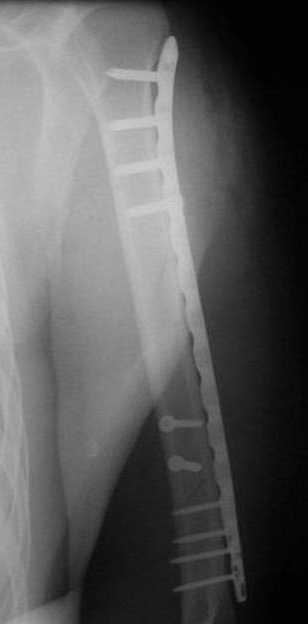

Р.S. Привожу клинический пример больного с огн. переломом бедра Густилло- Андерсон 111 А

Подход при 1,11, некоторых 111 А переломах "нетрадиционный -сберегательная хирургическая обработка, СОХРАНЕНИЕ всех костных отломков, первичный малоинвазивный остеосинтез LCP ( не нарушается периостальное и эндостальное кровоснабжение отломков, а при штифтовании нарушается эндост. кровоснабжение и риск медулярного остеомиелита), проточное дренирование, первичное закрытие ран, БЕЗ НАТЯЖЕНИЯ тканей или перв. отсроченные швы. При переломах 111В на первом этапе также СБЕРЕГАТЕЛЬНАЯ обработка с сохранением отломков и АВФ. Через две недели -МАЛОИНВАЗИВНЫЙ остеосинтез LCP